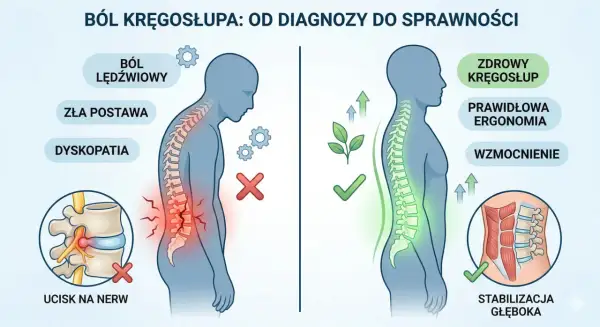

Ból korzeniowy kręgosłupa - Jak leczyć skutecznie?

Ból promieniujący z kręgosłupa? Odkryj skuteczne metody leczenia bólu korzeniowego: odciążenie, rehabilitację i kiedy działać pilnie. Sprawdź nasz poradnik!

Ból pleców przy schylaniu - Co oznacza i jak sobie pomóc?

Ból pleców przy schylaniu? Dowiedz się, co oznacza, kiedy iść do lekarza oraz jak bezpiecznie wrócić do sprawności. Sprawdź nasz poradnik!

Ból kręgosłupa przy chodzeniu i staniu - Co naprawdę pomaga?

Ból kręgosłupa przy chodzeniu i staniu? Odkryj przyczyny, rozróżnij przeciążenie od ucisku nerwu i dowiedz się, co naprawdę pomaga. Sprawdź nasz poradnik!

Dyskopatia lędźwiowa - Unikaj tych ruchów i wróć do formy

Masz dyskopatię lędźwiową? Dowiedz się, jakich ruchów unikać, by nie nasilać bólu i bezpiecznie wracać do aktywności. Sprawdź nasz poradnik!

Jak dbać o kręgosłup? Proste zasady dla zdrowych pleców

Odkryj, jak dbać o kręgosłup! Zmień nawyki, poznaj skuteczne ćwiczenia i dowiedz się, kiedy szukać pomocy. Zadbaj o zdrowe plecy już dziś!